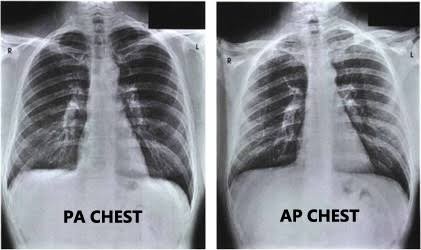

胸片的类型

从数据集中,可以找到三种类型的图像,PA,AP和Lateral(L)。L的很明显,但X光的AP和PA视图有什么区别?简单地说,在拍X光片的过程中,当X光片从身体的后部传到前部时,称为PA(后-前)视图。在AP视图中,方向相反。

通常,X光片是在AP视图中拍摄的。但是一个重要的例外就是胸部X光片,在这种情况下,最好在查看PA而不是AP。但如果病人病得很重,不能保持姿势,可以拍AP型胸片。

由于绝大多数胸部X光片都是PA型视图,所以这是用于训练模型的视图选择类型。